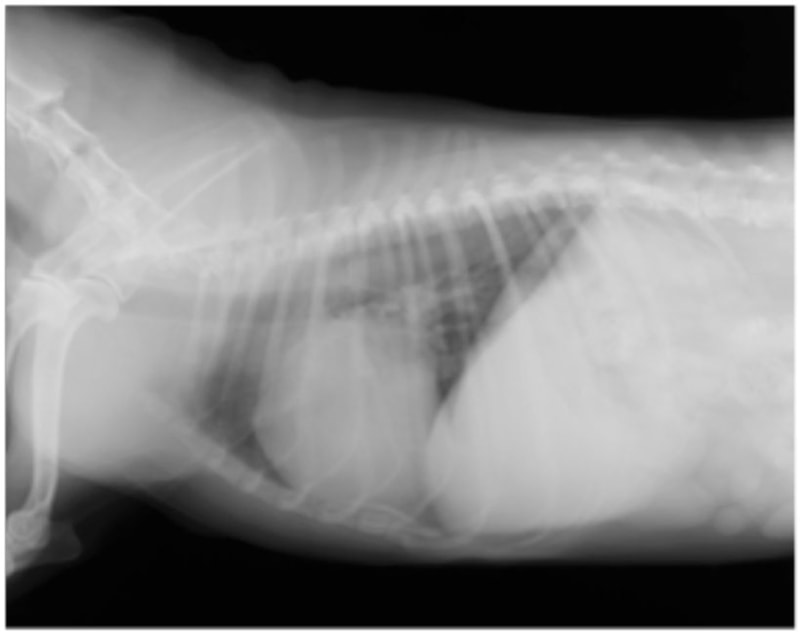

A:胸部レントゲン写真 正面像

B:胸部レントゲン写真 側面像

胸部レントゲン検査において重度の心拡大と肺水腫が認められた。超音波検査では、重度の僧帽弁閉鎖不全症、三尖弁閉鎖不全症、中程度の大動脈弁閉鎖不全症を合併していることが判明した。三尖弁逆流速度から肺高血圧症が示唆された。